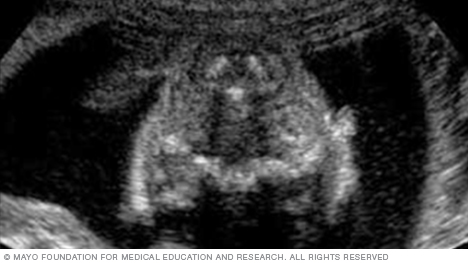

The image below shows all four chambers of the heart, as well as the heart valves. This type of image usually is taken during an ultrasound done between weeks 18 and 22 of pregnancy. Fetal ultrasound is used to check that the heart is working properly and to see if there could be any heart problems.